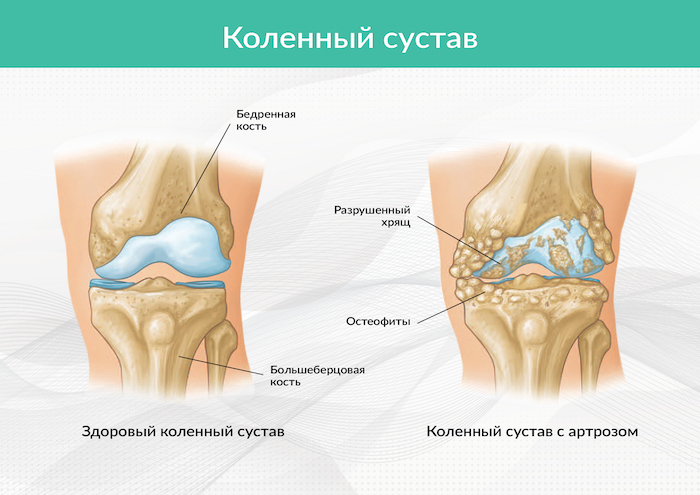

Рисунок 1. Расстояние между бедренной и большеберцовой костью в здоровом коленном суставе (слева) и сужение суставной щели из-за разрушения хрящевой прослойки с образованием остеофитов (справа).